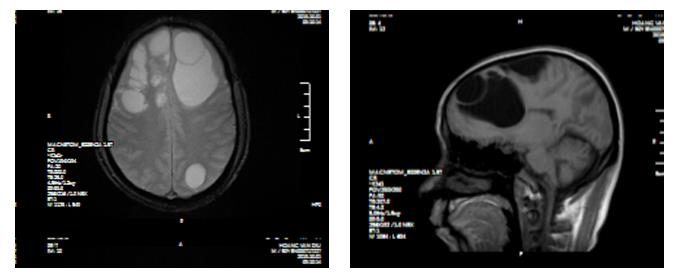

Hình ảnh phim chụp CT sọ não bệnh nhân có sán làm tổ trong não gây suy giảm trí nhớ.

Tại bệnh viện, kết quả chụp CT sọ não bệnh nhân cho thấy có ổ sán khổng lồ ở cả hai bán cầu trái gây phù não diện rộng. Bệnh nhân được chỉ định can thiệp ngoại khoa bằng phương pháp phẫu thuật.